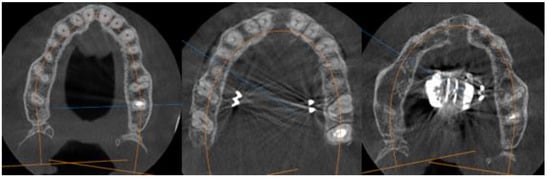

- Stage D or E palatal fusion (as seen in Angelieri et al. [18]) confirmed on CBCT prior to MARPE insertion;

2.1. Outcome Measures

2.2. Clinical Outcomes